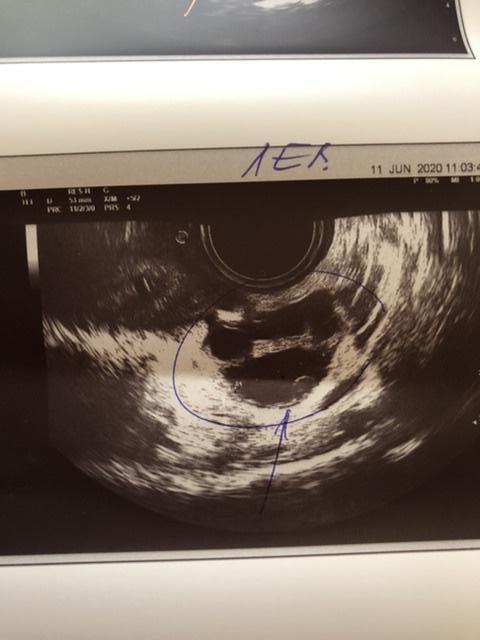

Идёт 4 цикл планирования , решила сходить на узи, на 1 сказали подозрение на полип и киста правого яичника, сегодня была на 2 узи. Кисты в Правом яичнике нет ! Правый яичник с фолликулами до 11 мм, а вот левый содержит доминантный фолликул 20 мм, как думаете когда будет овуляция ? Но , опять увидели это включение размером 7 на 4 мм, сказали с полипом не забеременеешь ! Вопрос кто делал гистероскопию ? Как она прошла ? Или может кто-то забеременел с полипом ? И все же как думаете когда совуляционирует левый яичник ? Эндометрий 10 мм это хороший показатель ?

Я ходила на 9 день размер 8 на 4 мм на 15 день 7 на 4 мм, иду к гинекологу и надеюсь чтоб все обошлось !

Спасибо ! Делала на 9 дц размер 8 на 4 мм, делала на 15 день цикла 7 на 4 мм, уменьшился ? Не понятно , если не полип то что это может быть ?